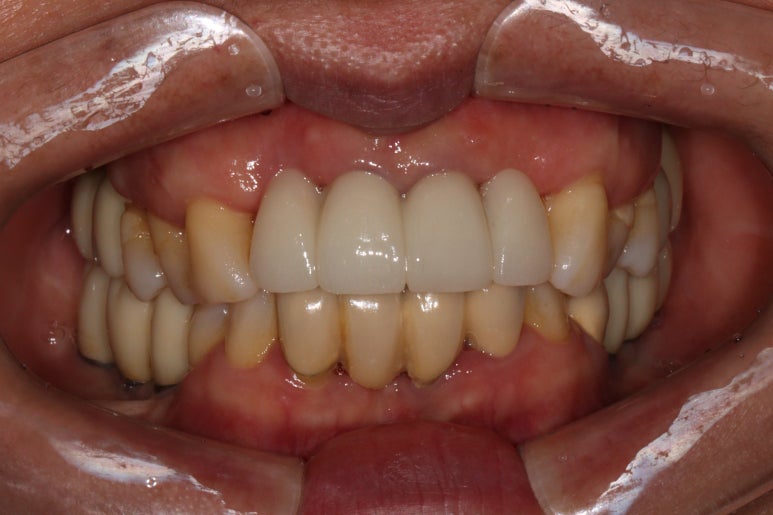

짜잔! 드디어 앞니 임플란트가 완성되었어요.

사실 저는 아래 치아와 비슷한 색으로 하고 싶었지만, 대부분의 환자분들은 도자기 같이 밝은 색이 나는걸 좋아하시죠 !!!! 지금 보시는 앞니 임플란트 보철물은 지르코니아 크라운입니다. 정확히 얘기하면 지르코니아 코어에 포세린 (도자기재질)을 붙인 PFZ 크라운입니다.

색상이 상당히 깊이가 있고, 모양도 보다 더 자연스러워진걸 보실 수 있을거에요.

신금호역 치과 백원장의 임플란트 치료의 하이라이트는 전후 비교겠죠?

최종 보철물 완성 후

아주 드라마틱한 변화를 보실 수 있을거에요!!!!

가장 우려했던 것은 고름이 나오던 치아들이 있었던 자리의 잇몸이 붕괴되면서 치아가 너무 길어지지는 않을까 하는 부분이었습니다.

그렇지만, 생각보다 조화롭게 보철물 제작이 가능하였던 것을 보실 수 있을거에요.

처음에 비하면 치석제거도 정~~~말 많이 되어 잇몸 컨디션도 아주아주 좋아진 상태입니다.